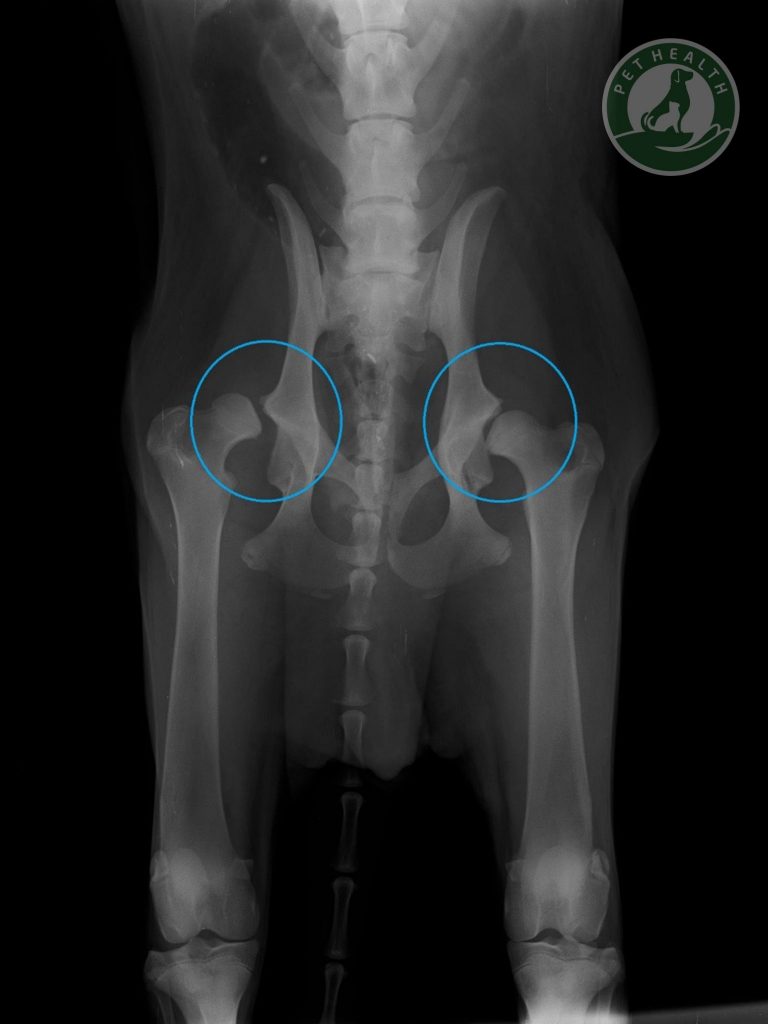

Cho dù người nuôi thú cưng ở Việt Nam chưa biết nhiều về chứng Loạn sản xương hông, nhưng thực tế là nó khá phổ biến. Nhiều thú cưng phát triển tình trạng này chỉ ở một bên hông, nhưng hầu hết các con vật bị ảnh hưởng đều gặp phải tình trạng đó ở cả hai bên khớp hông. Chẩn đoán loạn sản xương hông có thể được thực hiện bằng chẩn đoán hình ảnh như chụp X-quang